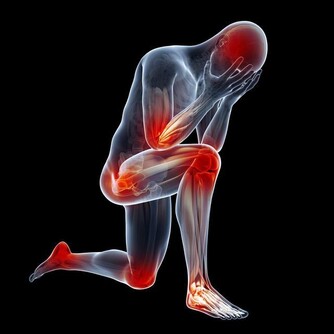

莧菜平衡酸鹼值,補血又使痛風消。莧菜有紅莧、白莧,應該大量推廣。

尿酸痛風的人,可以每天吃一碗莧菜湯,或像我們客家人用莧菜煮麵線,但是不要放吻仔魚。

莧菜能平衡酸鹼,你的尿酸痛風就會好。

不要吃冰的東西,不要吃香蕉,香蕉吃了痛風就發作,因為裡面有鉀離子。

莧菜補血,就是紅莧菜,又使痛風消,

所以每天用一碗面線、一把莧菜,保證不會體重增加,保證尿酸痛風全部消掉。